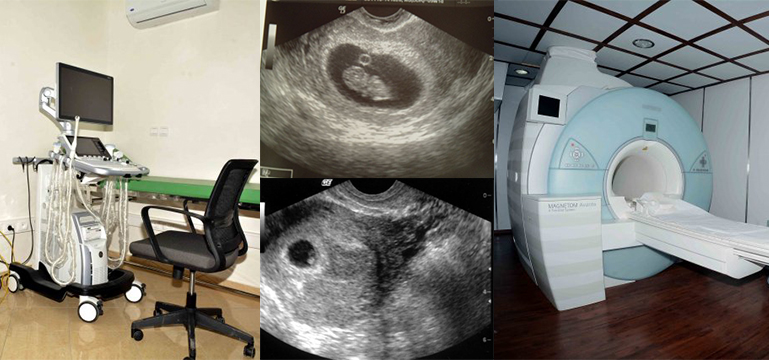

هناك أنواع عدة للأشعة التي تستخدم لإجراء التصوير الشعاعي لأغراض تشخيصية. فمنها أشعة آمنة على الحمل، مثل التصوير بالأمواج فوق الصوتية (Echographie) وما شابهها. ومنها ما ينطوي على خطورة محتملة، وبالأخص أشعة إكس (السينية) التي يعتمد عليها التصوير بالأشعة المقطعية.

وإذا لم تكن المريضة تعلم أنها حامل وخضعت إلى الأشعة السينية، فالأمر يصبح أمام احتمالين لا ثالث لهما، إذا ان التأثير المحتمل للأشعة على الجنين يكون مرهونا بقاعدة طبية تقول: (إما كل شيء، أو لا شيء). وهذ يعني أنه إما أن الأشعة ستؤثر على المضغة الجنينية كلياً فتوقف نموها ويحدث إجهاض مبكر، أو أن الأشعة لا تؤثر مطلقا على المضغة ويستمر الحمل بشكل طبيعي من دون أن تكون هناك فرصة لإصابة الجنين بتشوهات. فالأشعة السينية التي تتعرض لها الحامل قبل بلوغ عمر المضغة 8 أسابيع إما أن تقتل خلايا المضغة، واما لن تؤثر عليها مطلقاً.

وبما أن المرأة اكتشفت لاحقا أنها حامل في الأسابيع الأولى بعد خضوعها للأشعة المقطعية، فإنه إذا اتضح أن حملها ما زال موجوداً وأظهر التصوير بالأمواج فوق الصوتية وجود مضغة تنبض، فهذا معناه أن الأشعة المقطعية لم تؤثر مطلقا على الحمل، في هذه الحالة ينبغي عليها أن تتعامل مع حملها بلا مخاوف أو هواجس.